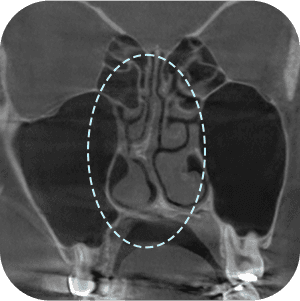

Apakah perlu dilakukan CT scan hidung?

AKarena ini adalah operasi revisi, kita perlu mendiagnosis dengan lebih tepat!

Analisis menyeluruh penting untuk operasi revisi hidung .

Tim medis operasi hidung di AB Plastic Surgery, secara akurat memprediksi prognosis dengan menganalisis dan mengidentifikasi kondisi secara rinci berdasarkan pengetahuan yang diperoleh dari melakukan berbagai operasi revisi hidung.

Karena analisis yang akurat

dapat dilakukan melalui 3D-CT! - 03